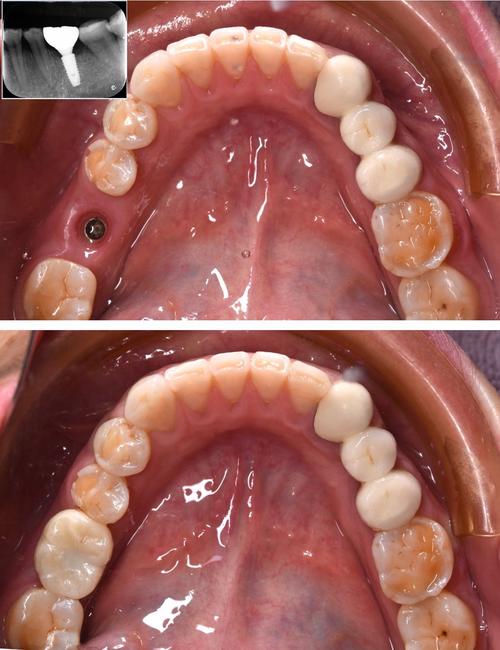

(图片来源网络,侵删)- 特点: 全瓷材料,颜色为白色或牙色,完全避免了金属色的透出问题。

- 应用: 主要用于对美观要求极高的前牙区,或者对金属过敏的患者,在骨质条件良好、咬合力不是特别大的情况下应用较多,目前是钛种植体的一个重要补充和替代选择。

(图片来源网络,侵删)